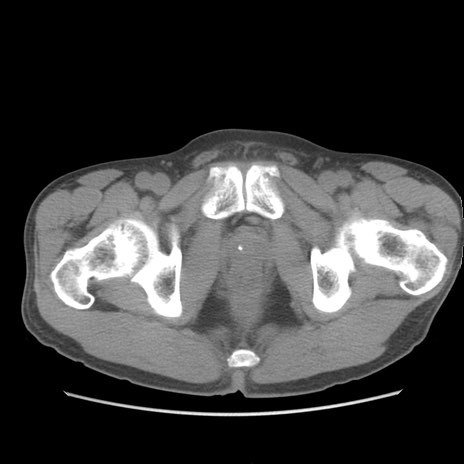

症例56 CT(横断像)

脂肪ウインドウ